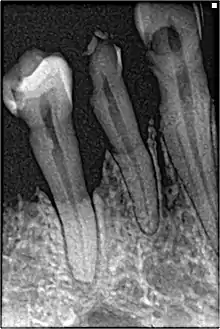

Perhaps the most serious oral condition that can arise is that of oral cancer. However, smoking also increases the risk for various other oral diseases, some almost completely exclusive to tobacco users. The National Institutes of Health, through the National Cancer Institute, determined in 1998 that "cigar smoking causes a variety of cancers including cancers of the oral cavity (lip, tongue, mouth, throat), esophagus, larynx, and lung."[101] Pipe smoking involves significant health risks,[109][110] particularly oral cancer.[111] Roughly half of periodontitis or inflammation around the teeth cases are attributed to current or former smoking. Smokeless tobacco causes gingival recession and white mucosal lesions. Up to 90% of periodontitis patients who are not helped by common modes of treatment are smokers. Smokers have significantly greater loss of bone height than nonsmokers, and the trend can be extended to pipe smokers to have more bone loss than nonsmokers.[112]

Smoking has been proven to be an important factor in the staining of teeth.[113][114] Halitosis or bad breath is common among tobacco smokers.[115] Tooth loss has been shown to be 2[116] to 3 times[117] higher in smokers than in non-smokers.[118] In addition, complications may further include leukoplakia, the adherent white plaques or patches on the mucous membranes of the oral cavity, including the tongue.[119]